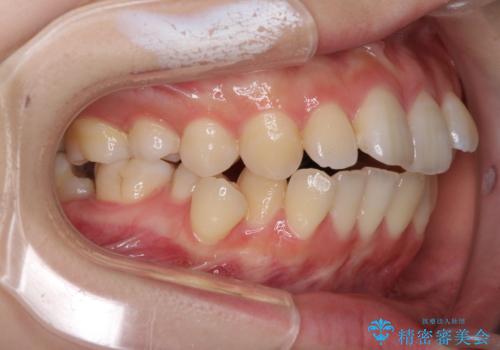

- 口元の突出感を気にして来院された患者様です。

上下左右の第一小臼歯4本を抜歯して口元を下げる治療計画としました。